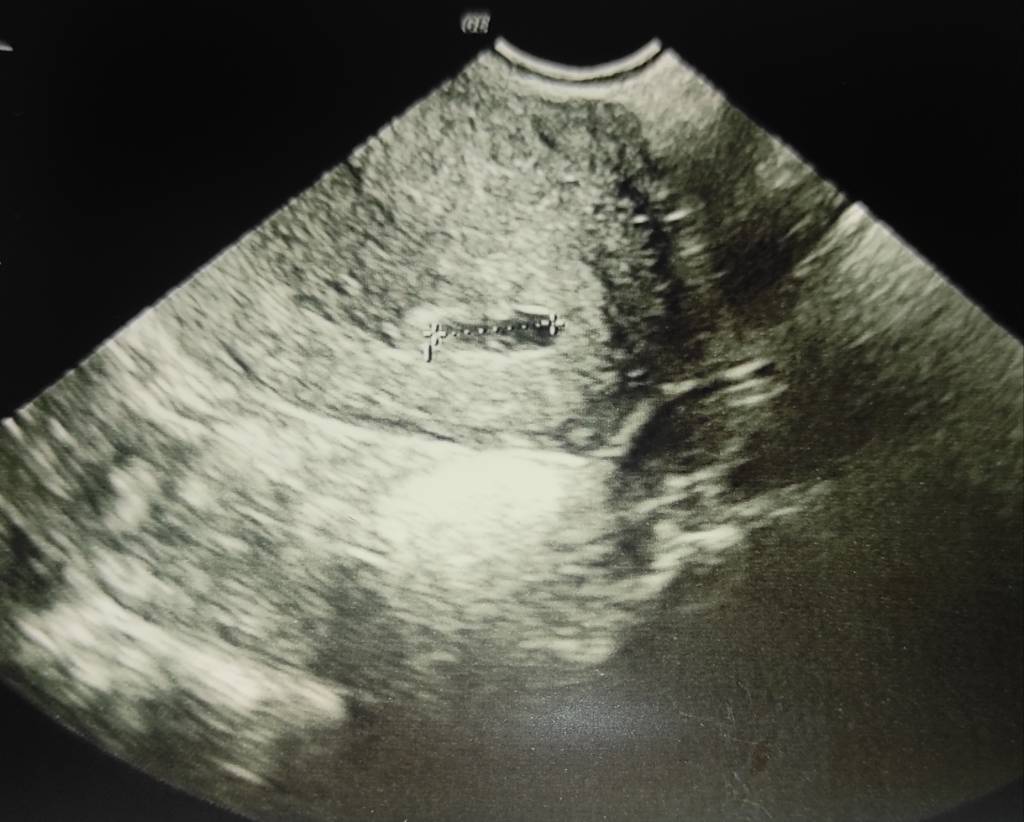

Lekarz znalazł strukturę ponad 1 cm i nie jest pewny co to, czy to pęcherzyk??

Czy mogło być tak że przez prawie pełny pęcherz pęcherzyk na USG mógł być zniekształcony i przez to lekarz nie mógł poznac? Lekarzami nie jesteście ale jakbym wstawiła zdjęcie to ktoś by powiedział czy to wygląda jak pęcherzyk ? Czy nie ma to sensu?

Jasne dam fotke. Myślę że pełny pęcherz nie ma znaczenia przy usg dopochwowym, samej czesto chce mi sie siku i wychodzi ok

1,32 cm

IMG_20201105_214140.jpeg